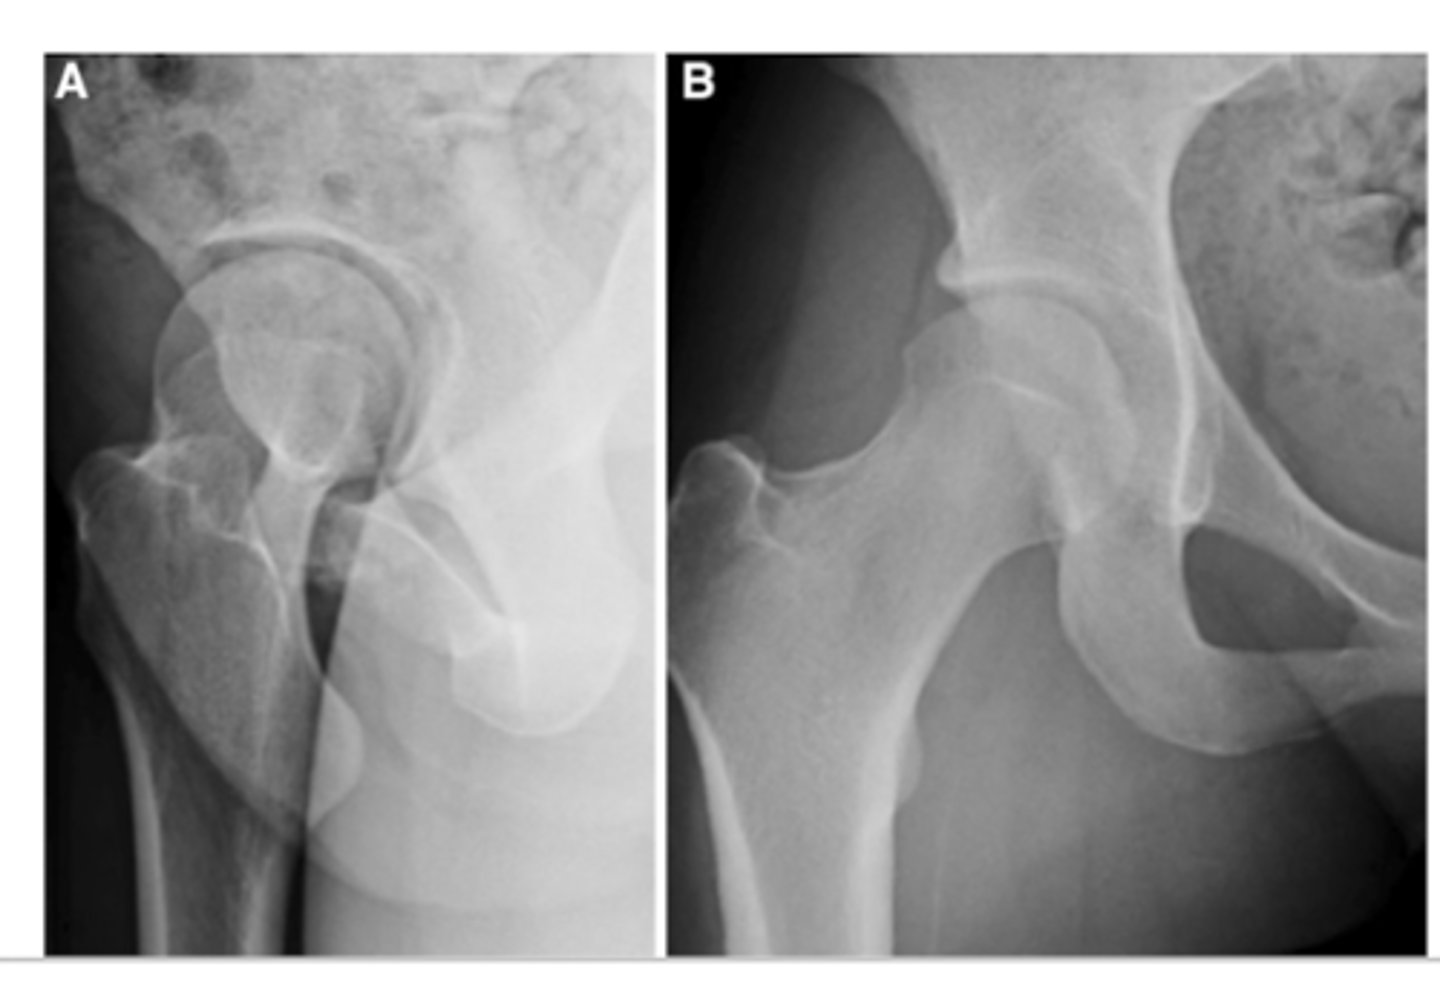

FAI arthroscopy

A pre op

B post op